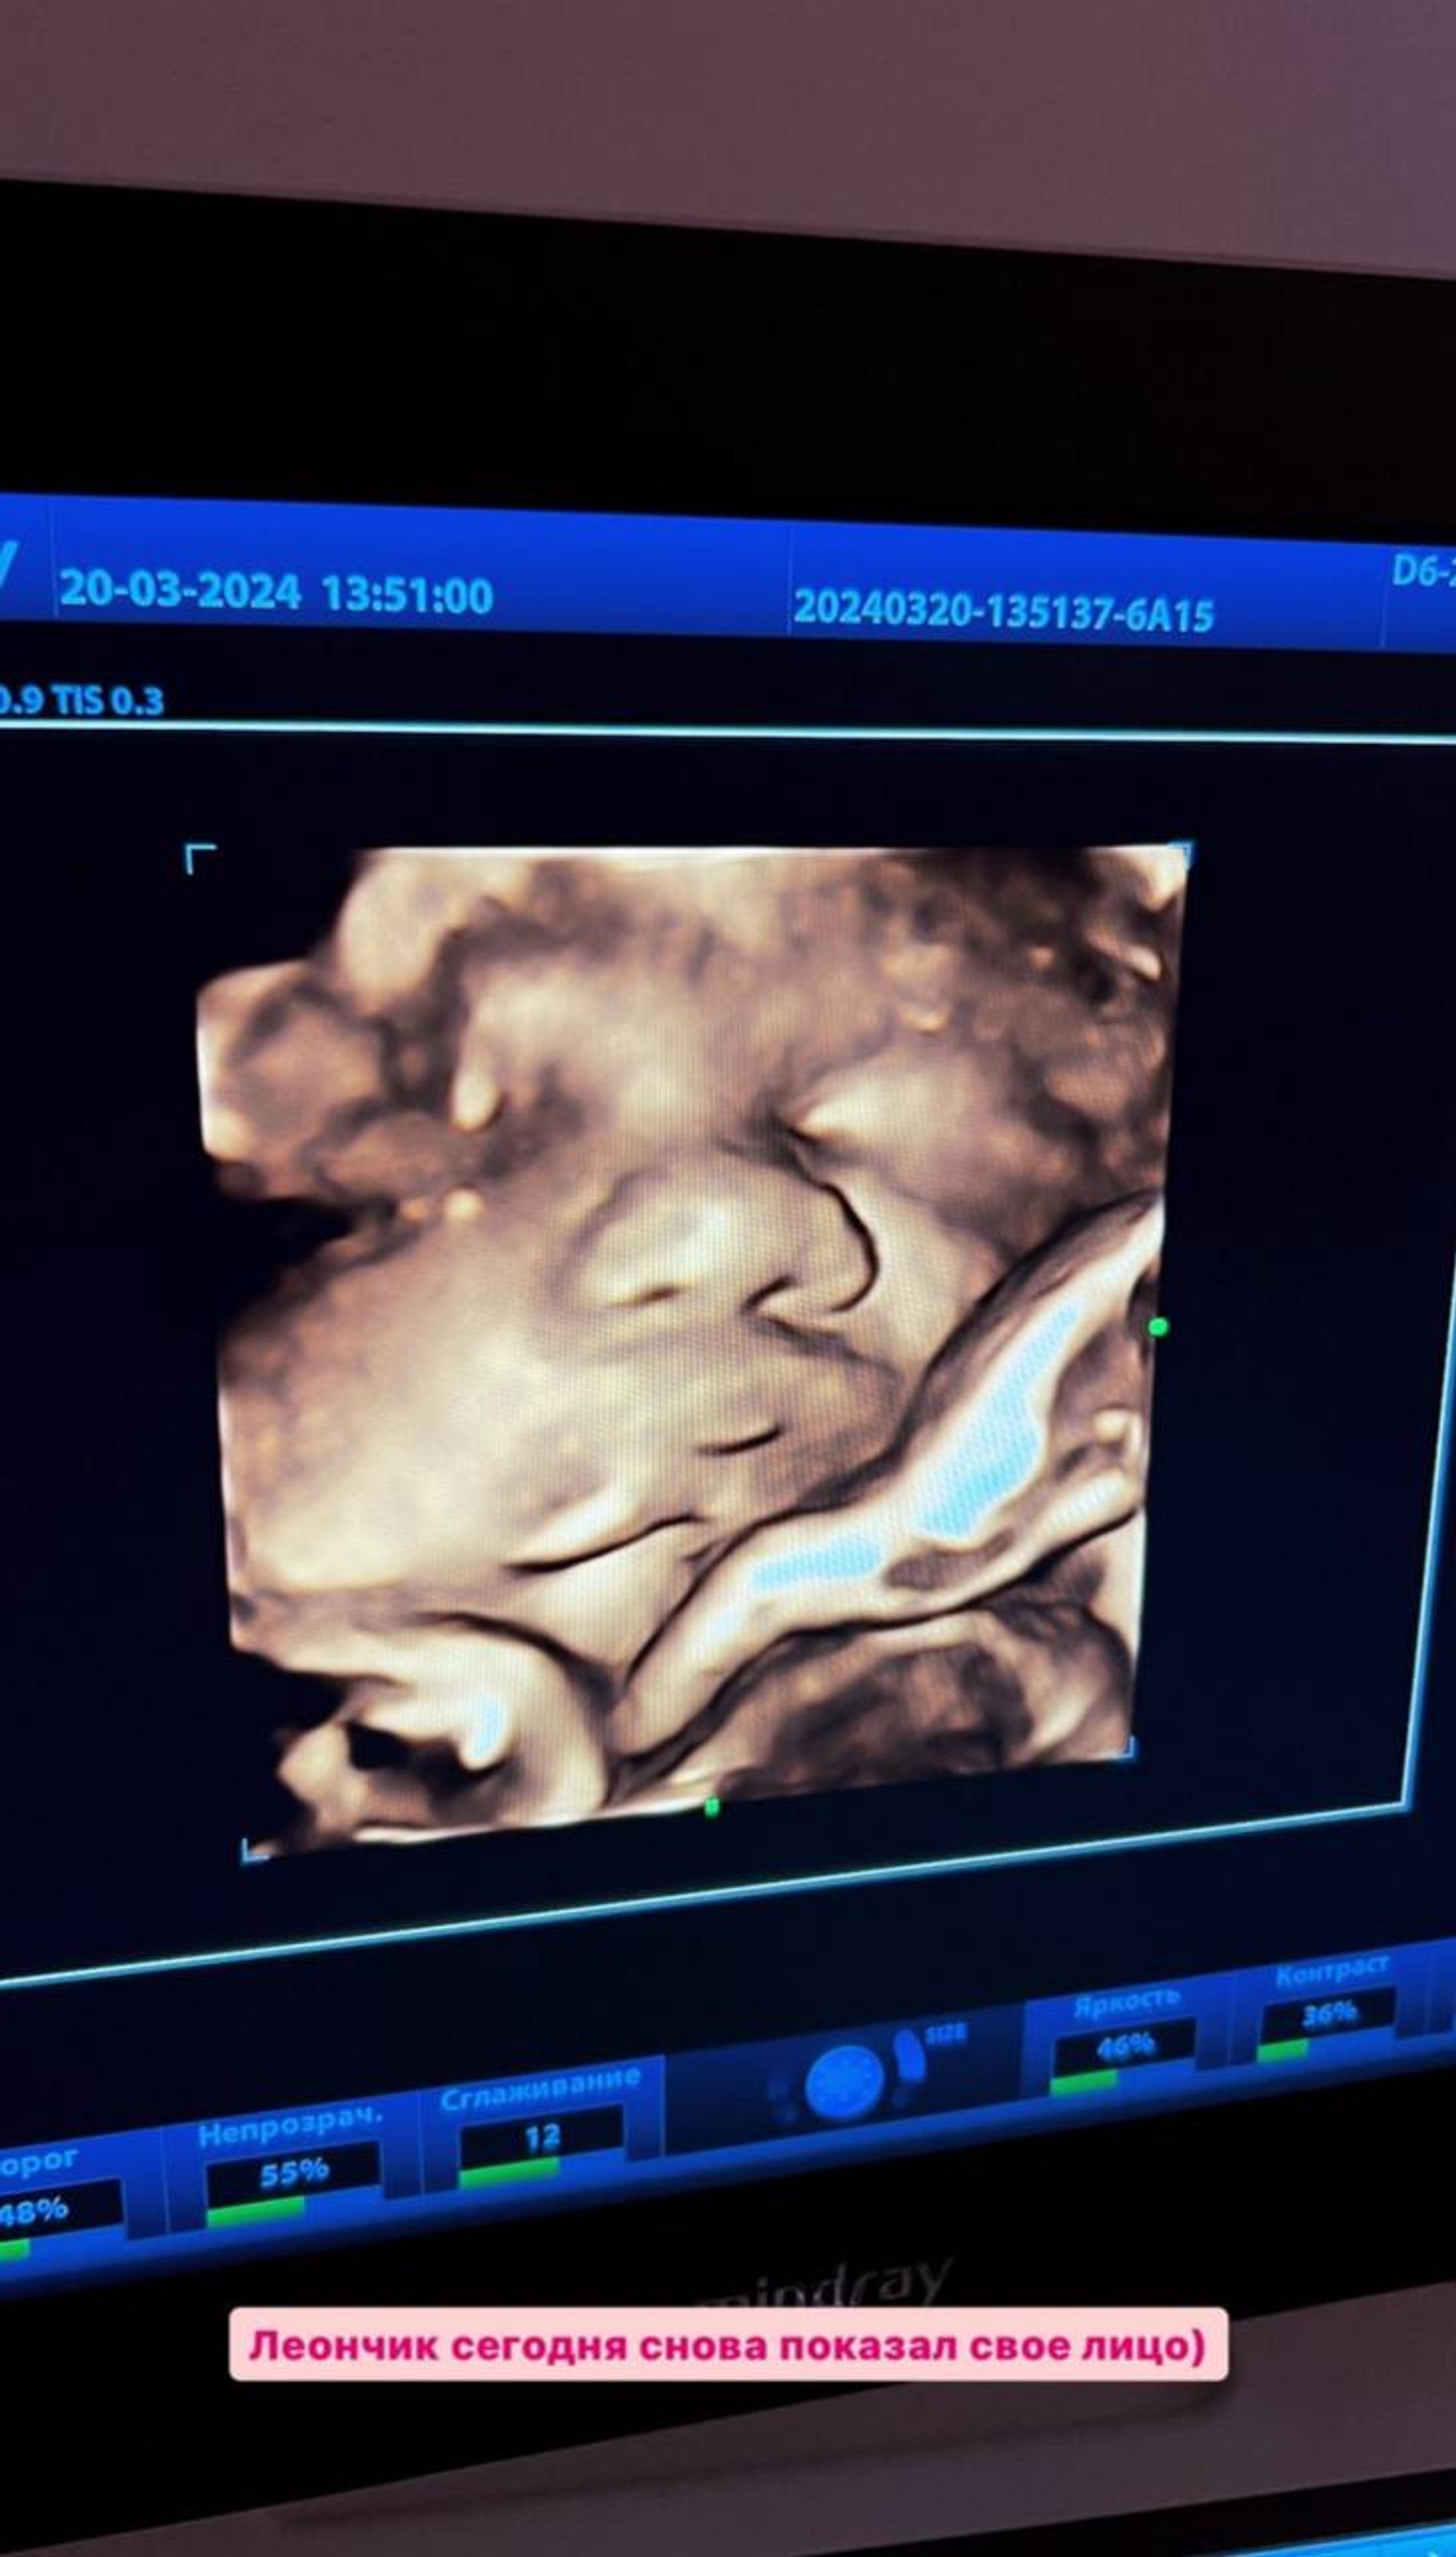

Звезда «Дома-2» Тигран Салибеков — опытный отец. Малыш, которого они ждут вместе с 21-летней Викторией Лысковец, для него четвертый. Тем не менее гордый папа не упускает возможности разделить с молодой возлюбленной радости подготовки к рождению ребенка. Накануне Тигран отправился с Викторией на плановый осмотр, о чем рассказал своим подписчикам. Девушке сделали КТГ и УЗИ. На второй процедуре блогеру подвернулась удачная возможность показать поклонникам, как сейчас выглядит малыш. «Леончик сегодня снова показал свое лицо, — радостно поделился Тигран. — Сделали, как моя бабушка говорит, фотокарточки».